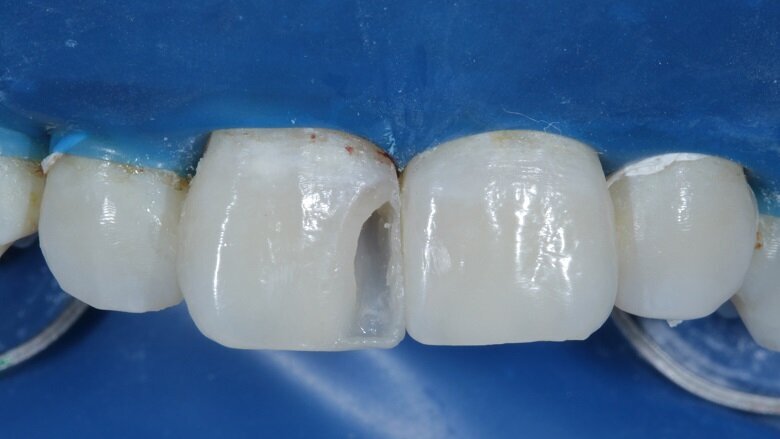

The shades that were selected were A2 Dentin, A2 Body and A2 Enamel. After this, isolation was achieved with a rubber dam (Fig 6). The caries of both 11 and 21 were excavated using a small round carbide bur (Fig 7). Primary and secondary bevels were given on tooth no 11 (Fig 8). After re-evaluation of the mesio-distal width of both the incisors, slight enameloplasty was done on tooth no 21 (Fig 9).

Fig 7: Excavation completed

Fig 9: Enameloplasty done on 21